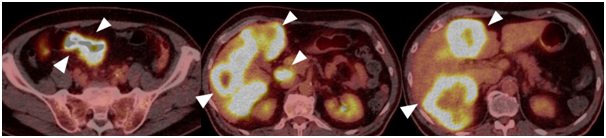

ㆍ 대장 및 직장암의 병기 설정을 위한 양전자 방출 단층촬영(PET)

일반적으로 대부분의 대장 및 직장암은 암의 증식 속도가 빠르며 이로 인하여 포도당 유사체를 이용한 양전자 단층 촬영에서 강한 섭취를 보이게 됩니다.따라서 악성종양을 영상화하는 데 유용한 포도당 유사체를 이용한 양전자 방출 단층촬영은 대장암 및 직장암의 초기 병기설정을 보다 정확하게 하는 데 도움이 됩니다.

64세 남자 환자로 결장암으로 진단받고 전이 병변에 대한 평가를 위해 포도당 유사체 양전자 방출 단층촬영 영상입니다.결장 부위에 강한 포도당 유사체 섭취 병변이 관찰되며 결장암 병변으로 판단이 됩니다. 간에 강한 포도당 유사체 섭취를 보이는 여러 병변들이 관찰되며 간전이로 판단이 됩니다.또한 간 주변에 림프절 전이로 보이는 병변이 함께 관찰되고 있습니다.환자는 초기 진단시에 적절한 병기 설정이 되었고 수술 대신 항암치료를 시작하였습니다.